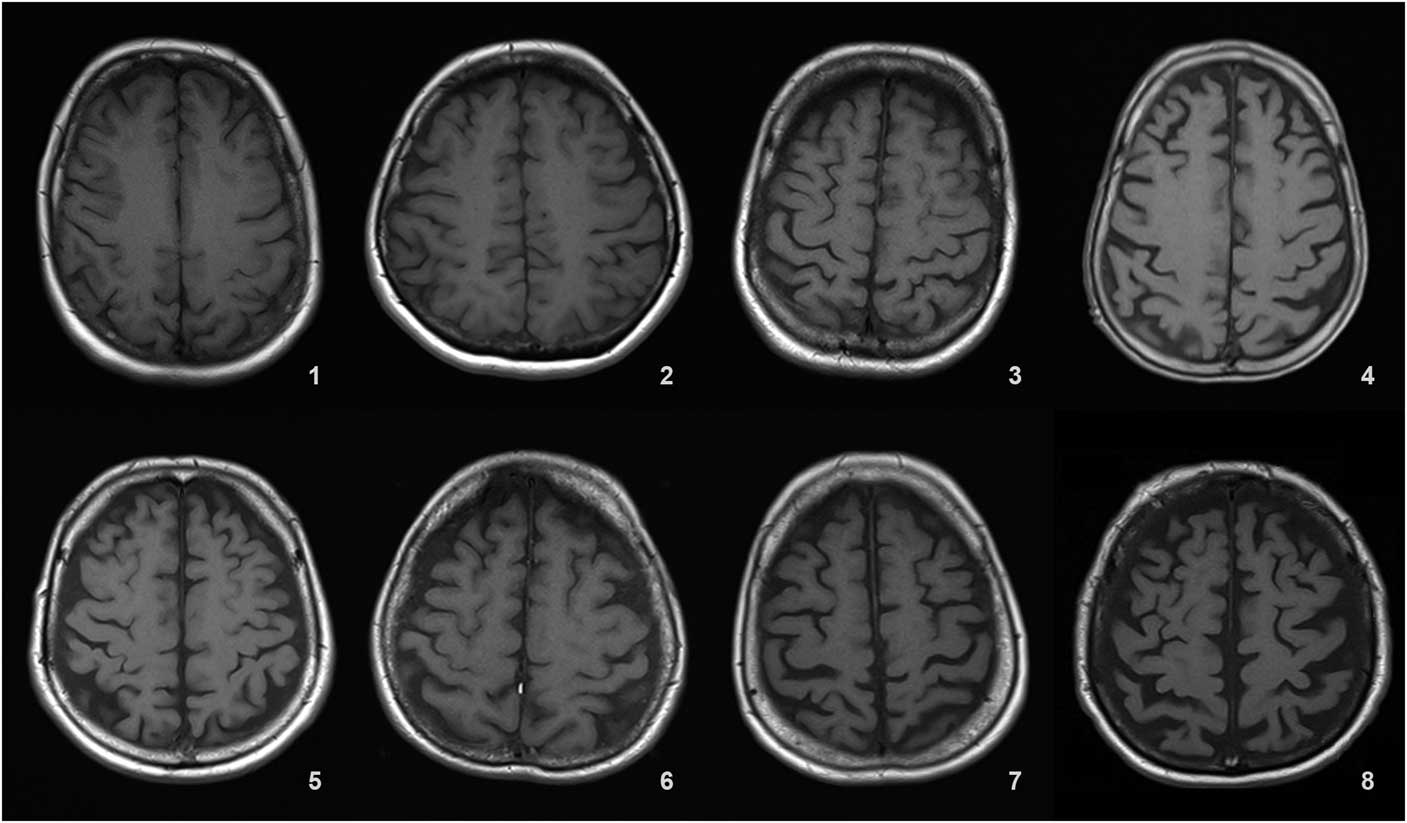

Sulcal atrophy (SA) was graded in a 0–9 range based on the widths of the central sulci, interhemispheric fissure, and other cortical sulci on the axial T1 (repetition time [TR]=673 ms, echo time [TE]=12 ms, 3 or 5 mm slice thickness, 0.6 mm gap) image corresponding to the slice level where central sulci is best viewed (most similar to the shape of inverted omega).

Details of the proposed scale are given in Table 1. For grading the SA, VA, and MTA, a reference data set was created from cranial MRIs of 30 subjects who were admitted to the clinic owing to complaints other than forgetfulness, but they were not included in the study (Figures 1–3). An exemplary MRI scan of a patient graded with PWMH=4 and SCWMH=3 can be seen in Figure 4.

Figure 1 Reference MRIs corresponding to sulcal atrophy grades between 1-8.